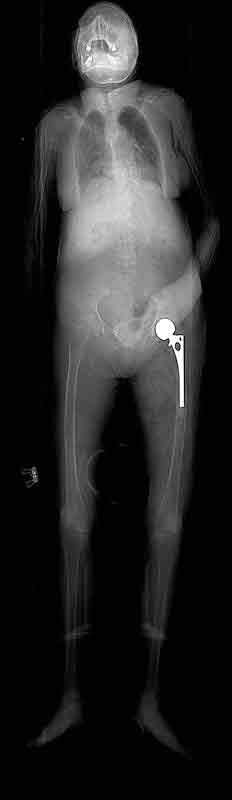

The image below is the scout film of cadaver 33487. Notice that the left hip joint has been replaced with a prosthetic joint consisting of a femoral stem attached to a ball that sits inside a prosthetic cup.